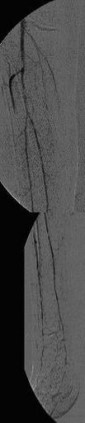

Nach perkutaner transluminaler Angioplastie (PTA) der Unterschenkelgefäße

(Bild 4 von 4)